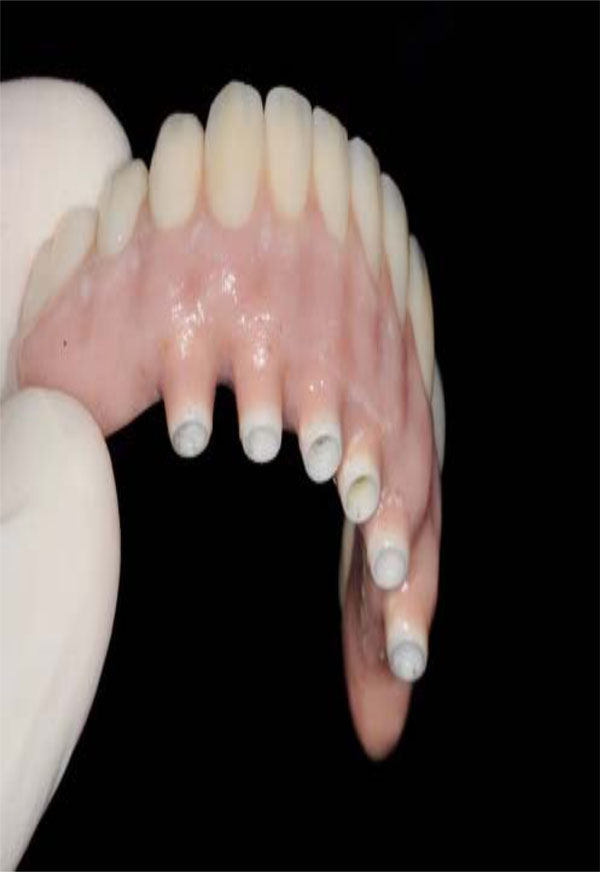

Esthetic demands tend to be more dramatic with maxillary prostheses than mandibular prostheses (Fig. 3). As per Zarb and Schmitt, unlike mandibular implant prostheses were hygienic type designs have proven to be functionally and esthetically acceptable, maxillary implant prostheses demand different sized and shaped labial/buccal flanges that may or may not compensate for optimal esthetics, phonetics, and masticatory function (Fig. 4). Additionally prosthetic gingival tissues are often required due to resorptive patterns of edentulous maxillae. Resorptive patterns in maxillae are dissimilar to mandibular resorption pattern: maxillae resorb superiorly, posteriorly, and medially: mandible resorbs inferiorly, anteriorly, and laterally [26, 27].

Intaglio surface of maxillary hybrid has been custom designed in order to improve esthetics and phonetics.